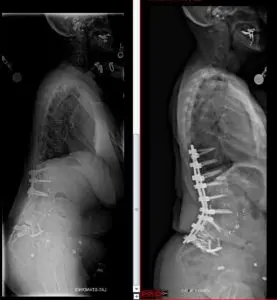

Treatment: L4 pedicle subtraction osteotomy and spinal fusion from T10 to the pelvis

“We made a detailed surgical plan, measuring the curve of her whole spine and spinopelvic angles and custom designed the curve of the rods. We had the advantage of using a robot to plan every screw placement prior to the surgery,” explains Li.

“Because her spine was fused straight, I had to first break down the fused spine or fracture it,” says Li.

Li then made a wedge-shaped cut, removed the L4 pedicle and then closed the gap to create a 25-degree curve in the patient’s spine. “The patient was on a bed that can flex and extend during the surgery, which helped us to close the gap and give her a more natural curve,” he says.

Outcome: Much improved spine alignment and no pain

After a period of rehabilitation and physical therapy to restore her mobility, the patient was able to walk upright and was completely pain-free in the back at a follow-up appointment six months after the surgery. It is first time in the last 15 years that she does not need pain medication.